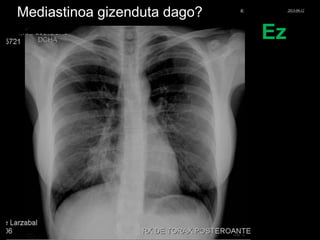

Mediastinoa gizenduta dago?

Ez